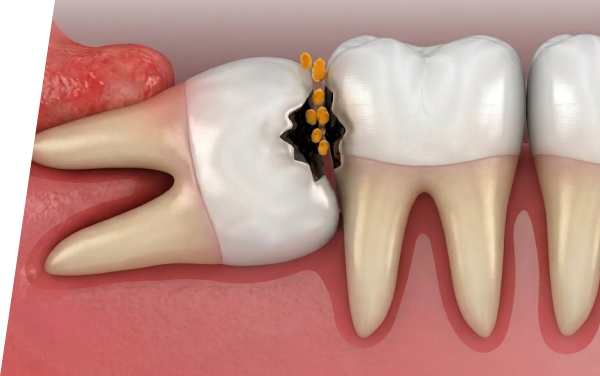

放置すると・・・

親知らずの生え方によっては、さまざまなトラブルにつながることがあります。

- Q3 親知らずは虫歯になる前に抜いた方がいいですか?

-

A3

親知らずの状態によって判断が異なります。まっすぐ生えて問題なく噛める場合は、必ずしも抜歯の必要はありません。一方で、磨きにくく炎症やトラブルを繰り返す場合は抜歯をおすすめします。放置すると手前の歯にも影響することがあるため、歯科医院での検査が重要です。